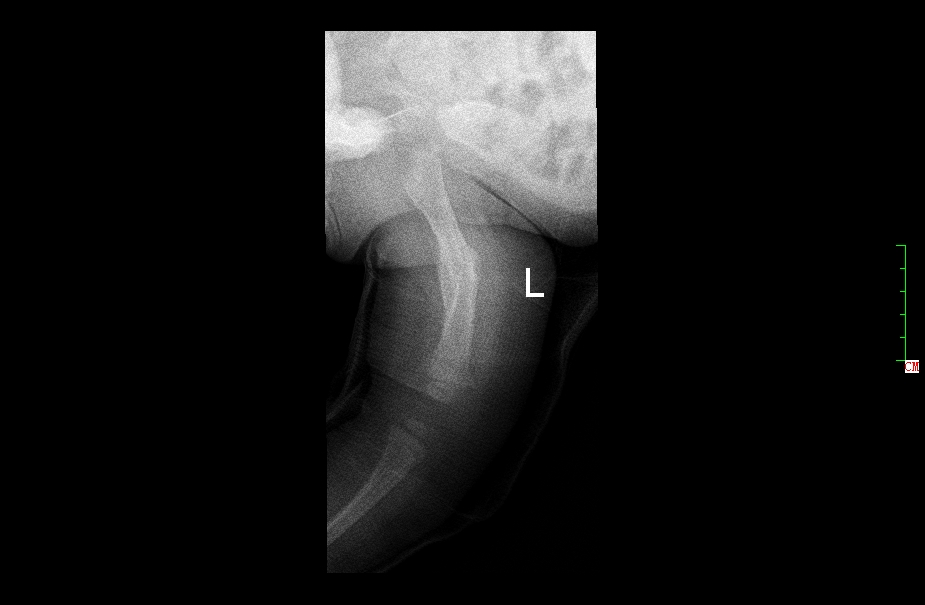

3月女婴股骨骨折正位片

3月女婴股骨骨折侧位片

2 月后复查正位片

2月后复查侧位片

1年后复查正位片,已完全愈合,自行矫形至正常